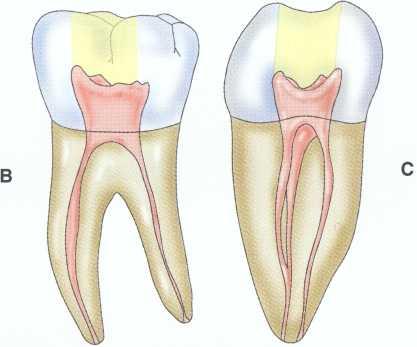

Unroo fing the Chamber

Unroofing the chamber and removing the coronal pulp facilitates the clinician's ability to visualize the chamber floor and aids in locating the canals. Complete removal of tissue and debris prevents discoloration and subsequent infection.

Unroofing the chamber and removing the coronal pulp (in vital cases) allow the clinician to see the pulpal floor. In cases of patent canals, most or all of the canal orifices may be easily located before the chamber is completely unroofed, but the clinician may nevertheless miss canals. In cases of calcification, performing these procedures increases the clinician's ability to visualize the pulpal floor and read the road map to the canal orifices detailed in the subtle color changes and patterns of calcification left by the receding pulp. This is extremely difficult or impossible to do through a "mouse hole" en-dodontic access.

Removal of the Coronal Pulp

Removal of the coronal pulp so that the canals may be located is necessary in cases with vital pulp. One advantage of removing the coronal pulp is that the radicular fragments may hemorrhage slightly, aiding in location of the canal orifices. This is especially useful in maxillary molar cases for locating the second mesiobuccal (MB2) canal.